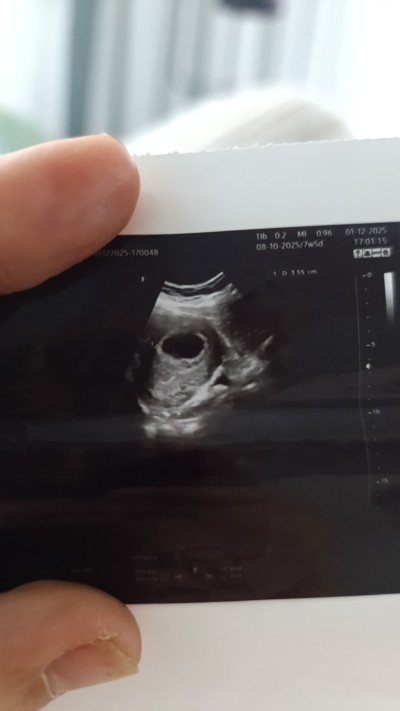

Merhaba, cevabınız için teşekkür ederim. Kesemi gördü doktor fakat içinde bebek yok, kalp atışı mevcut değil die kürtaj yapmak istediğini söyledi. O yüzden yazma gereği duydum. Sizce beklemeli miyim? Hatta buda ultrason kagidimiz .

image

Kesen sağlıklı bir keseye benziyor sakın acele etme bekle biraz en az bir hafta daha bekle  haata doktorunu değiştir bazı doktorların cihazı iyi değil

Kese şuan büyük ve bebek oluşması gerekiyordu dedi 2-3 doktora ve özel hastaneye gitmiş olmama rağmen . Ve kürtaj denildi. Ama doktorun birisi de kesenin içerisinde organa benzeyen bir şey var bu canlanadabilir canlanmayadabilir dedi. Yani inanın ne yapacağımızı şaşırdık. Kendi doktoruma daha randevuma var. Cuma günü için gelmemi söyledi. İlk gittigimde çok küçük olduğunu keseyi gördüğünü fakat içerisinde ufak bir parça gördüğünü de eklemişti. Ama ben 4 gün ufak bir kanama yüzünden hastanede yattım. Bugünde kesenin var olduğunu fakat kalp atışı olmadığını bebeğin oluşmadığını ve kürtaj olmamı söylediler. Çevremdeki insanlar da çok normal diyor. 9-10 haftaya kadar bekle deniliyor

Biraz daha bekle derim en azından 8. Haftaya kadar ama kese oluşmuş içi boş ise yapacak birşey yok doktorlar ne derse doğrudur ama şimdiye kadar 14 mm olması gerekirdi kalp atışı olmalıydı dk 150 kez hatta belki geç döllenmiş olabilir bekle bakalım